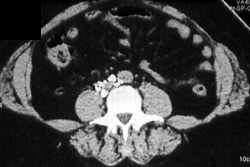

Diagnosis

Normal CT Urogram